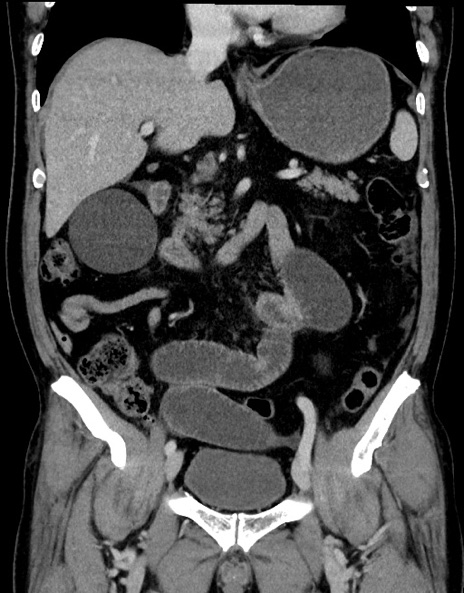

横断像

【症例】70歳代男性

【主訴】腹痛

【現病歴】今朝から腹痛あり。全体的に痛い。特に左上の方。排ガスが今日はない。冷や汗が出る。

【既往歴】直腸癌術後

【身体所見】左側腹部〜上腹部に圧痛あり。腹膜刺激症状明らかなではない。軽度反跳痛。左下腹部に術後瘢痕あり。

【データ】WBC 7700、CRP 0.02